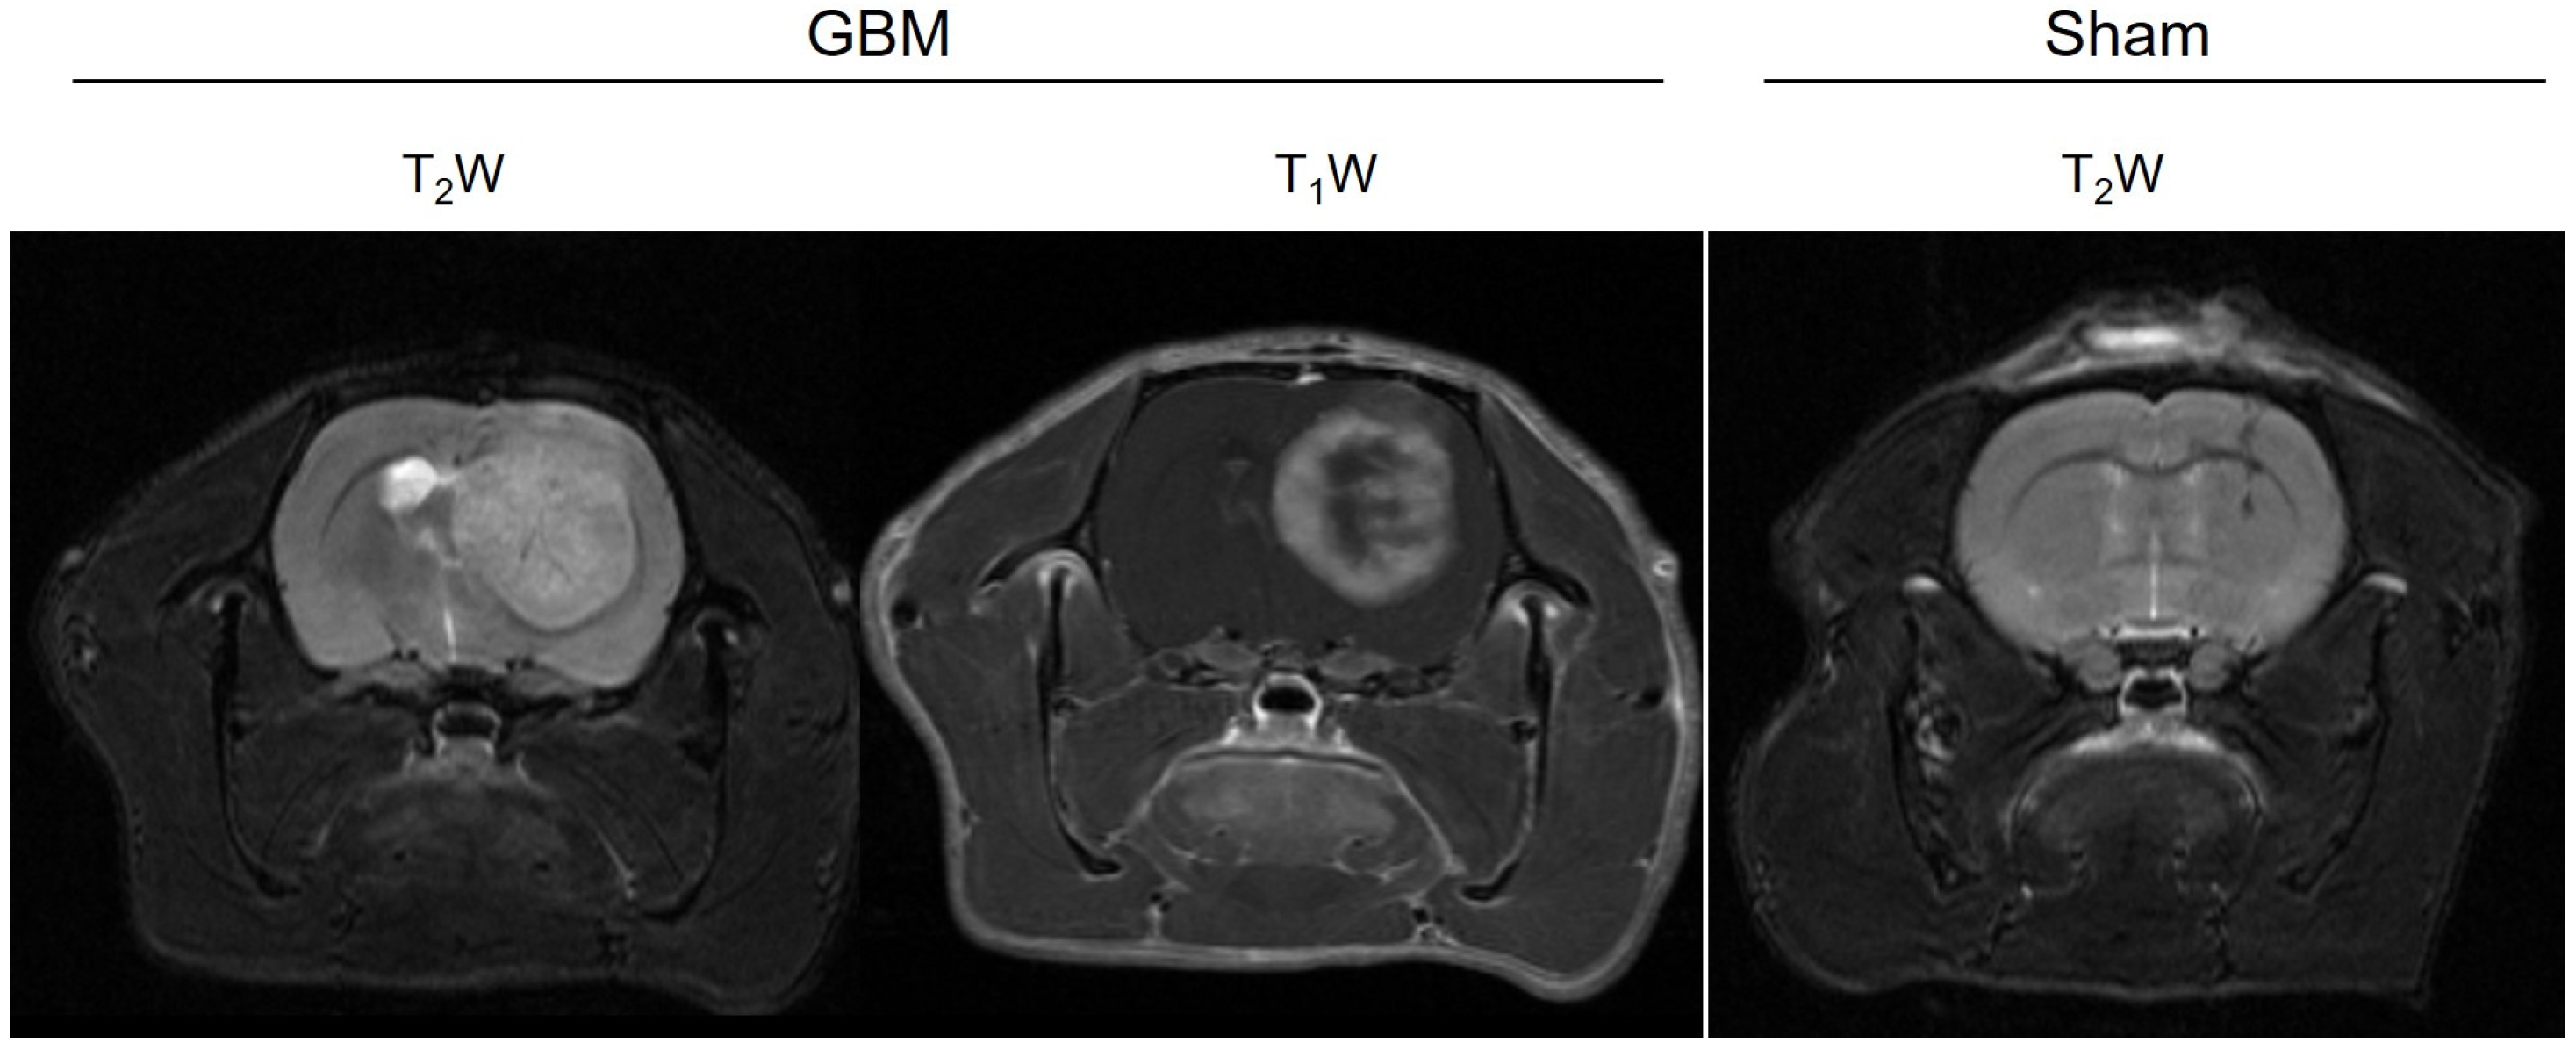

3.1. MRI Studies

3.1.1. Relaxometry